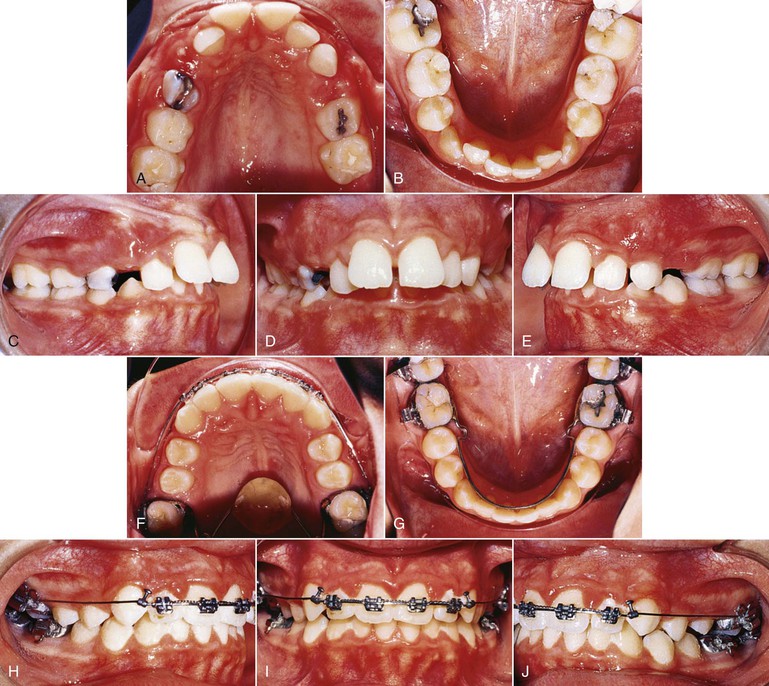

Another appliance that can be used with either patient compliance or patient noncompliance is the jig. The jig can be easily fabricated at chairside and used to correct either bilateral or unilateral Class II, Division 1 malocclusions (Fig. 12-6). In patients with poor compliance, the appliance can be tied in using long nickel-titanium (Ni-Ti) coil springs with an external tubing to minimize patient discomfort. These springs are very small in diameter and do not cause more discomfort than the SAIF springs. The SAIF spring is bulky, compared to the Ni-Ti spring (Fig. 12-7), and it can be tied from the mandibular first or second molar to the maxillary canine hook. Figure 12-6 shows an example of a patient treated with a unilateral jig.

Figure 12-6 Patient with a unilateral Class II, Division 1 malocclusion treated with a jig. The maxillary left canine was blocked out and could not erupt. A–E, Pre-treatment records showing Class II, Division 1 subdivision left. F–J, Final records after 12 months of treatment. No exposure of the unerupted canine was performed and the canine erupted as soon as space was created.